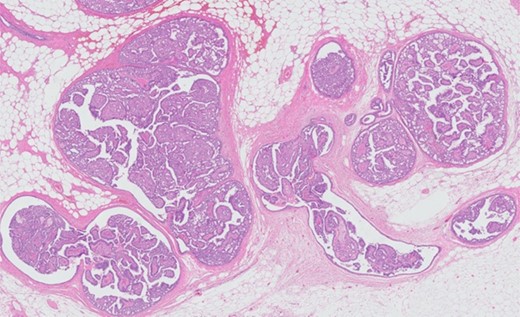

Ultrasonography showed a long-shaped solid structure with lobular architecture. Additional mammography showed a lobulated structure behind the nipple with a diameter of ∼1.5 cm without microcalcifications (BIRADS III). Histological and immunohistochemical examination of a core needle biopsy demonstrated an intraductal proliferation compatible with an IP. Subsequently, surgical excision of the lump was performed under general anesthesia. Microscopy of the resected specimen confirmed the diagnosis of an IP of ∼1 cm with a free margin of <1 mm. Sections through preexistent breast tissue showed central dilatated cystic structures with a papillary proliferation of epithelial cells with partly cylindrical morphology and heterogenous (non-monotonous) appearance. We found no indication of invasive growth (Figure 1). Immunohistochemistry showed 10% MIB-1 activity. SMA and keratin 5/6 staining demonstrated the presence of myoepithelial cells throughout the lesion with a heterogenous random staining pattern in the keratin 5/6 slide supporting the diagnosis of a benign proliferation (Figure 2).

Hematoxylin and eosin stain (HE) overview. HE microphotograph with an overview of the lesion characterized by cystic and papillary architecture. No indication of invasive growth.